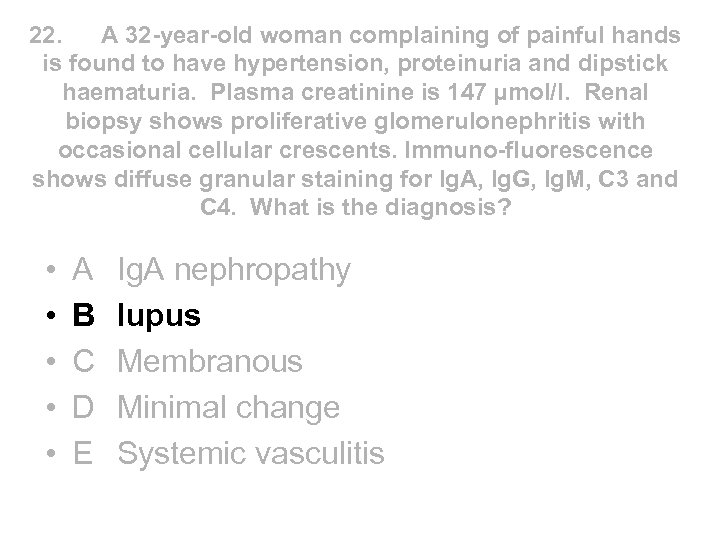

22. A 32 -year-old woman complaining of painful hands is found to have hypertension, proteinuria and dipstick haematuria. Plasma creatinine is 147 µmol/l. Renal biopsy shows proliferative glomerulonephritis with occasional cellular crescents. Immuno-fluorescence shows diffuse granular staining for Ig. A, Ig. G, Ig. M, C 3 and C 4. What is the diagnosis? • • • A B C D E Ig. A nephropathy lupus Membranous Minimal change Systemic vasculitis

22. A 32 -year-old woman complaining of painful hands is found to have hypertension, proteinuria and dipstick haematuria. Plasma creatinine is 147 µmol/l. Renal biopsy shows proliferative glomerulonephritis with occasional cellular crescents. Immuno-fluorescence shows diffuse granular staining for Ig. A, Ig. G, Ig. M, C 3 and C 4. What is the diagnosis? • • • A B C D E Ig. A nephropathy lupus Membranous Minimal change Systemic vasculitis

22. A 32 -year-old woman complaining of painful hands is found to have hypertension, proteinuria and dipstick haematuria. Plasma creatinine is 147 µmol/l. Renal biopsy shows proliferative glomerulonephritis with occasional cellular crescents. Immuno-fluorescence shows diffuse granular staining for Ig. A, Ig. G, Ig. M, C 3 and C 4. What is the diagnosis? • • • A B C D E Ig. A nephropathy lupus Membranous Minimal change Systemic vasculitis

22. A 32 -year-old woman complaining of painful hands is found to have hypertension, proteinuria and dipstick haematuria. Plasma creatinine is 147 µmol/l. Renal biopsy shows proliferative glomerulonephritis with occasional cellular crescents. Immuno-fluorescence shows diffuse granular staining for Ig. A, Ig. G, Ig. M, C 3 and C 4. What is the diagnosis? • • • A B C D E Ig. A nephropathy lupus Membranous Minimal change Systemic vasculitis

Renal Immunofluorescence and Electron Microscopy • Ig. A nephropathy - mesangial deposition of Ig. A • Lupus - full house IF of Ig. G, Ig. A, Ig. M, C 3, C 4 • Membranous - granular staining for Ig. G along GBM with subepithelial immune complex deposits “spikes” on silver staining • Minimal change - foot process fusion on EM only • AASV - no immunoglobulin deposition - described as pauci immune to distinguish from lupus in patient with crescentic nephritis

Renal Immunofluorescence and Electron Microscopy • Ig. A nephropathy - mesangial deposition of Ig. A • Lupus - full house IF of Ig. G, Ig. A, Ig. M, C 3, C 4 • Membranous - granular staining for Ig. G along GBM with subepithelial immune complex deposits “spikes” on silver staining • Minimal change - foot process fusion on EM only • AASV - no immunoglobulin deposition - described as pauci immune to distinguish from lupus in patient with crescentic nephritis